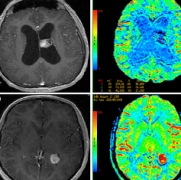

素来以生长迅速、预后差、复发程度较高而著称的 胶质母细胞瘤 (GBM)是当之无愧的致命癌症之一,也被称为脑瘤终结者。 可怕的胶质母细胞瘤 根据国家癌症研究所的数据,它也被称...

控制脑肿瘤生长,重在早发现、早诊断、早治疗

颅内肿瘤 ,统称或俗称脑肿瘤或脑瘤,可发生于任何年龄段,其中以20-50岁人群较为多见。 较新美国国家癌症中心数据报告显示,无论男性还是女性,脑肿瘤的发生率都排在全身肿瘤的...